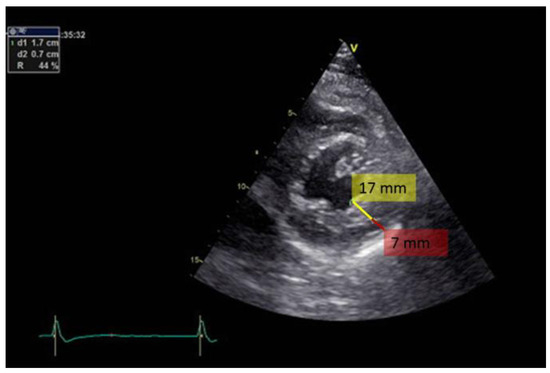

Transthoracic bidimensional echocardiography (2D- TTE) is the method of choice for diagnosing LVNC (Figure 2, Figure 3 and Figure 4). Three basic echocardiographic criteria have been proposed to define LVNC: a thick myocardium with a non-compacted layer and a compacted one; prominent trabeculations; and deep endomyocardial recesses.

Figure 2.

Bidimensional transthoracic echo- cardiography, short axis view of the left ventricle apex. Note the excessive trabeculation in the infero-postero- lateral region. Red line indicates the distance from the epicardial line to the beginning of the trabeculae (7 mm) and yellow line marks the thickness of the trabeculae (17 mm).

Several echocardiographic derived algorithms for diagnosing LVNC have been proposed [3,26,27]. The first echocardiographic criterion has defined ventricular wall non-compaction as the ratio X / Y < 0.5, where X represents the distance from the epicardial surface to the trabecular recesses and Y is the distance from the epicardial surface to the peak of trabeculae, measured in parasternal short axis for the apex and apical sections for the left ventricular free wall [3]. Others have proposed a ratio between non-compacted and compacted myocardium greater than 2:1 at end systole, in apical short axis section, in the absence of other cardiac disorders [26] for the diagnosis of LVNC. The trabeculae are usually situated at the apex / lateral wall, medium wall / inferior wall of the left ventricle. Most of the non-compacted segments are hypokinetic. Stollberger et al. [27] defined LVNC as the presence of more than three trabeculae in the left ventricular wall, with trabeculae situated at the apex, visible in a single imaging plan. The flow between the inter-trabecular recesses can be identified by using the color Doppler method. A fourth criterion has been proposed by Belanger et al. [28], who diagnosed LVNC using planimetric echocardiography to measure the trabeculae in apical 4 chambers section. They divided the patients by the area of left ventricular non-compaction into 3 groups: mild (< 2.5 cm2), moderate (2.5-4.9 cm2) and severe (> 5 cm2). Based on a study on 380 patients, 15.8% were diagnosed with LVNC. However, their criteria have not been validated as there was no correlation with the modified Jenni et al. criteria.